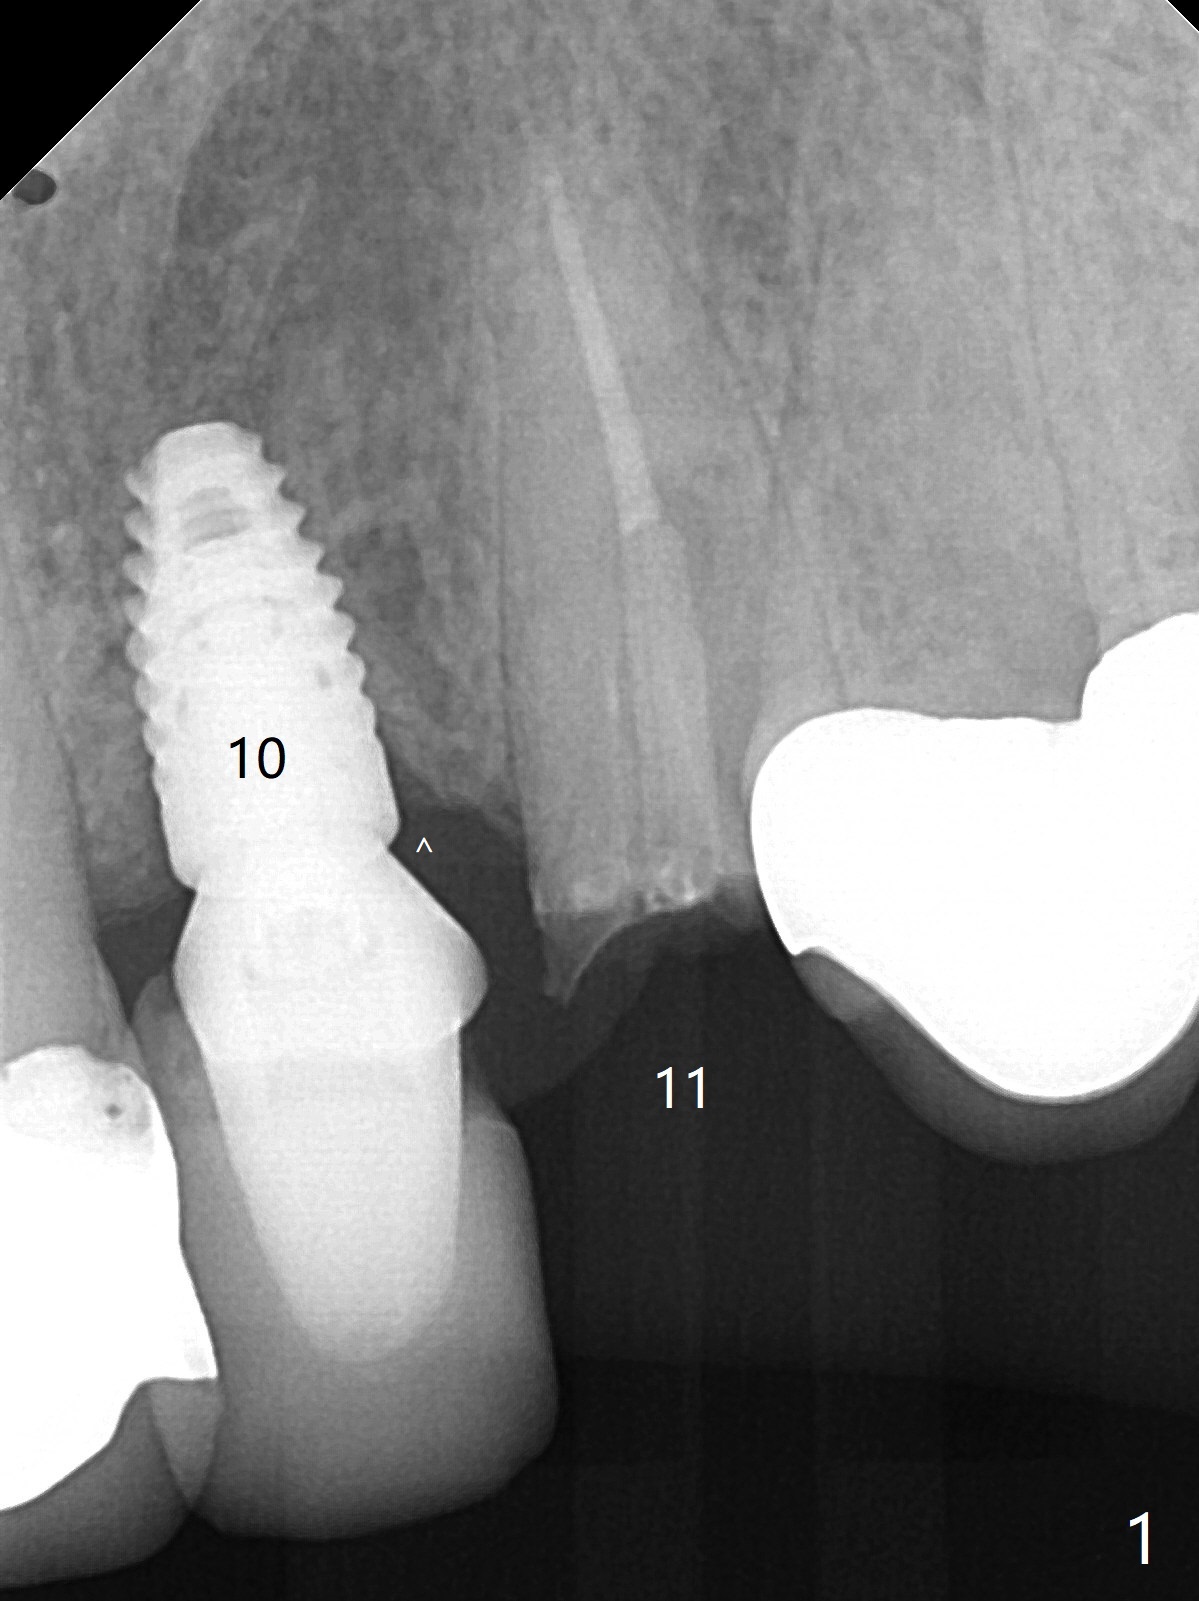

A 57-year-old woman presented to office with dislodged canine crown 10 months earlier (Fig.1). It was cemented. It dislodged again lately. She decides to have an implant and mentions looseness of the implant crown of the lateral incisor. Gingival recession is severe at #10 (Fig.2), while #11 has subgingival fracture (Fig.3). The recession is related to suboptimal angulation and buccal placement of the fixture (Fig.4), while the implant at #11 will be narrow and be placed with sufficient remaining buccal and palatal bone (Fig.5). Socket shield may be done. Prepare gingival retractors. In fact socket shield is not done because of caries in the root stump.